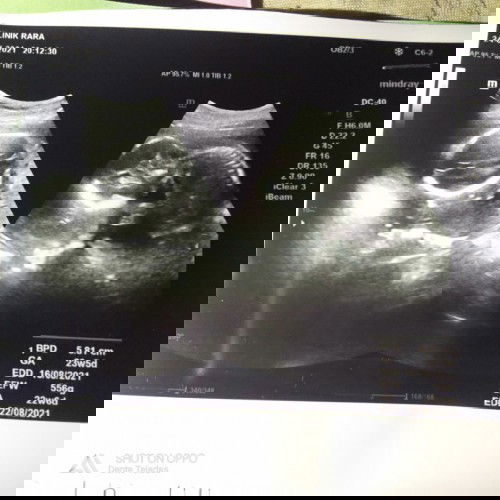

Bingung...perkiraan lahir menurut http 8desrmber,tpi liat hasil usg,,hpl nya 22agustus

karena anda usg di usia kehamilan yg sudah besar. maka dari itu pentingnya usg di trimester awal buat nentuin hpl yg bisa dibilang sesuai dengan hpht. 2x mau punya anak enggak pernah ada yg mleset dengan hpl sesuai hpht maupun usg.

salah menghitung hpht mungkin bunda , saya haid tidak teratur tanggal,nya , waktu USG hpl 27 agustus , tpi berdasarkan hpht hplnya 6 agustus , selisih 3 minggu😅 nggak ampek berbulan²

tak ada yg pasti kapan bayi lahir bund. hpl hanya acuan namanya juga (hari perkiraan lahir), hasil usg biasanya karena dari ukuran janin, hpht ya sesuai hitungan haid hari pertama bunda